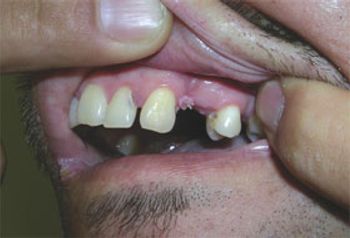

Heart disease, stroke, and cancer are leading causes of death in men, but they present to primary care with a variety of other, often difficult-to-diagnose concerns. Take this week’s photo quiz to test your knowledge of men’s health issues.

A homeless man with lithophagia; hereditary trichoepithelioma; IBD mimics: can you answer this week's quiz questions about these and 2 other disorders?